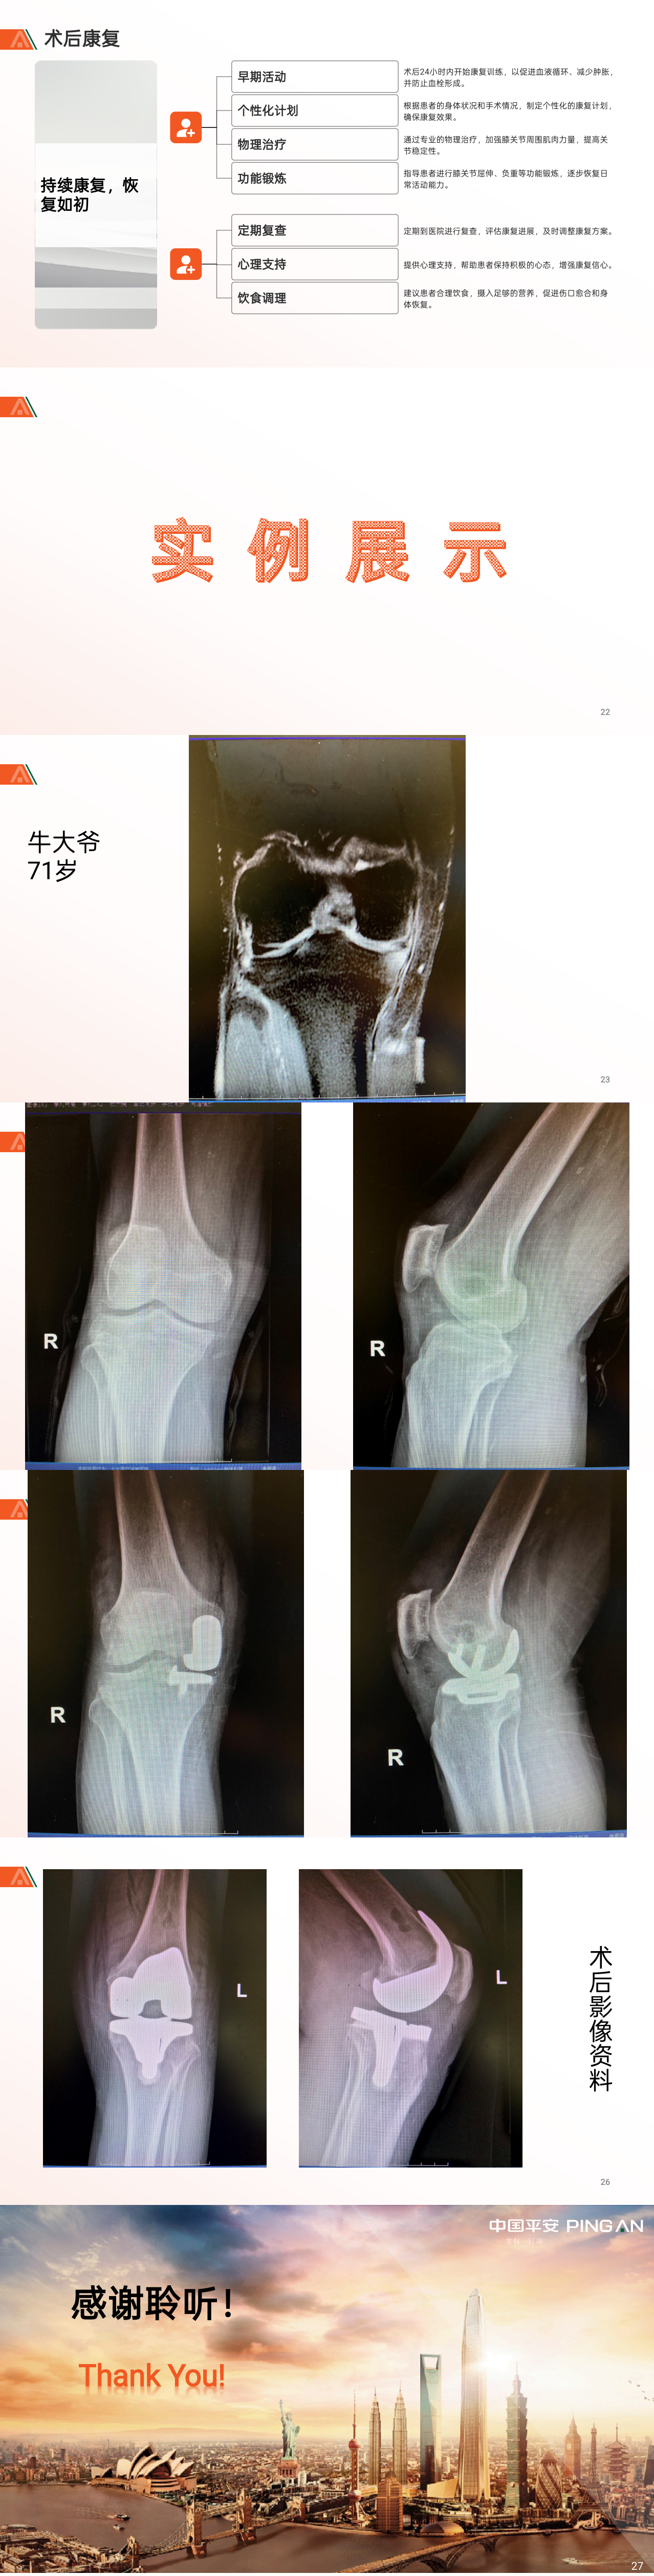

作品所属领域:骨科

山东省 北大医疗淄博医院

张腾 关节外科 主治医师